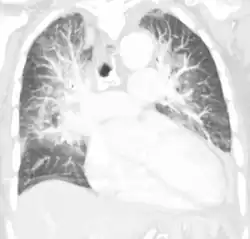

Chest X-ray has been used for many years to diagnose pulmonary edema due to its wide availability and relatively cheap cost.[4] A chest X-ray will show fluid in the alveolar walls, Kerley B lines, increased vascular shadowing in a classical batwing peri-hilum pattern, upper lobe diversion (biased blood flow to the superior parts instead of inferior parts of the lung), and possibly pleural effusions. In contrast, patchy alveolar infiltrates are more typically associated with noncardiogenic edema.[3]

Lung ultrasounds, employed by a healthcare provider at the point of care, is also a useful tool to diagnose pulmonary edema; not only is it accurate, but it may quantify the degree of lung water, track changes over time, and differentiate between cardiogenic and non-cardiogenic edema.[36] Lung ultrasound is recommended as the first-line method due to its wide availability, ability to be performed bedside, and wide diagnostic utility for other similar diseases.[4]

Especially in the case of cardiogenic pulmonary edema, urgent echocardiography may strengthen the diagnosis by demonstrating impaired left ventricular function, high central venous pressures and high pulmonary artery pressures leading to pulmonary edema.